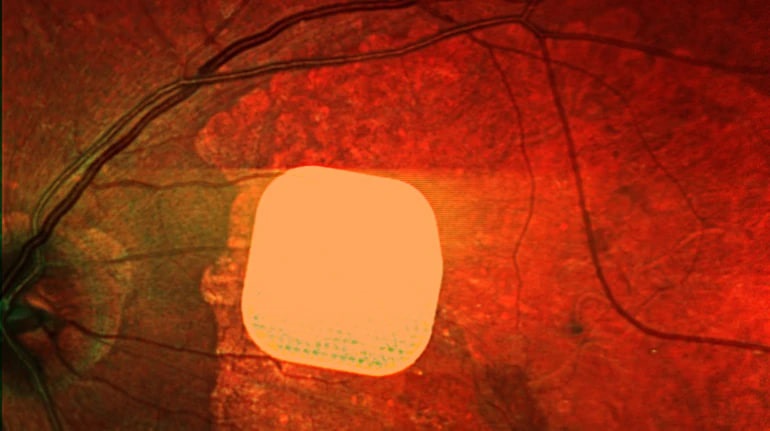

Британські лікарі з лондонської клініки Moorfields Eye Hospital спільно з колегами з інших європейських медичних закладів успішно випробували новий електронний імплант Prima, який допомагає частково відновити зір пацієнтам із макулодистрофією. Цей мікрочип розміром лише 2×2 міліметри встановлюють під сітківку ока і підключають до системи окулярів доповненої реальності. Після операції та адаптації до нового виду зору, 84% пацієнтів знову змогли розрізняти літери, цифри та слова. Лікарі вважають, що ця технологія відкриває нові можливості для людей із важкими зоровими порушеннями, допомагаючи покращити їхню якість життя.